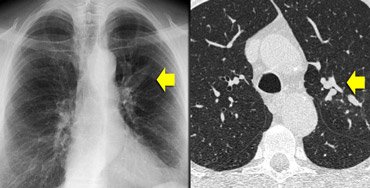

Aspergilose broncopulmonar alérgica

Tomografia computadorizada (TC) do tórax em um paciente com aspergilose broncopulmonar alérgica (ABPA): sombra em "dedo de luva" devida à impactação mucoide na bronquiectasia central em um paciente com asma

Do The Radiology Assistant: Chest - HRCT Part 1; usado com permissão